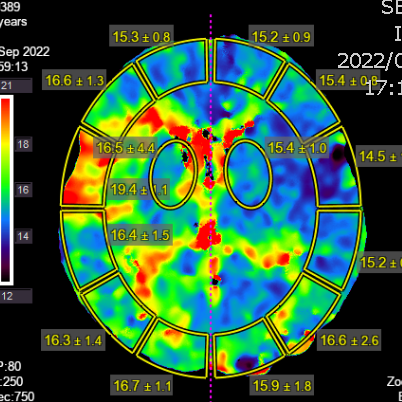

右侧相对低灌注

灌注明显改善,支持进一步随访

灌注比术前进一步改善